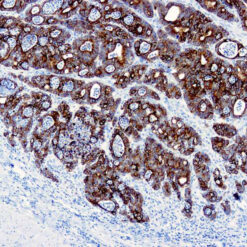

CD7 is expressed by most peripheral blood T cells, NK cells, and all thymocytes. It is one of the earliest surface antigens on T and NK-cell lineages. The antibody is a useful aid for classification of T-cell malignancies.

| Clone | CBC.37.8 |

| Positive Control Tissue | Tonsil |